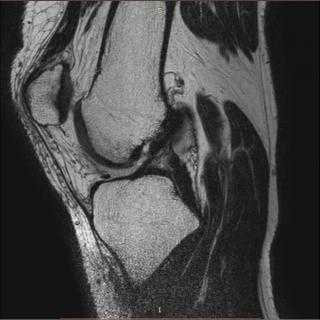

Первая из серии аксиальных МР-томограмм правой голени в режиме Т1, полученная непосредственно над коленным суставом. Аксиальная МР-томограмма правой голени в режиме Т1, полученная непосредственно ниже коленного сустава. Первая из серии аксиальных МР-томограмм левой голени в режиме Т1, полученная непосредственно над коленным суставом. Аксиальная МР-томограмма левой голени в режиме Т1, полученная непосредственно ниже коленного сустава. Аксиальная МР-томограмма в режиме Т1: правая голень на уровне проксимального большеберцово-малоберцового сустава. Обратите внимание, что подошвенная мышца все еще представлена мышечной частью, лежащей перед латеральной головкой икроножной мышцы. Аксиальная МР-томограмма правой голени в режиме Т1, полученная на уровне проксимального ме-тафиза. На этом уровне от малоберцовой кости берет свое начало камбаловидная мышца. Срез выполнен слишком проксимально для визуализации большеберцового начала камбаловидной мышцы, поскольку все еще видна подколенная мышца. Подошвенная мышца теперь представлена сухожилием, лежащим между камбаловидной мышцей и медиальной головкой икроножной мышцы. На этом уровне задняя большеберцовая мышца визуализируется в виде раздвоенной структуры, берущей свое начало как от большеберцовой, так и малоберцовой кости. Между двух точек прикрепления визуализируются передние большеберцовые сосуды, проходящие в направлении переднего фасциального ложа. Аксиальная МР-томограмма в режиме Т1: левая голень на уровне проксимального большеберцово-малоберцового сустава. Обратите внимание, что подошвенная мышца все еще представлена мышечной частью, лежащей перед латеральной головкой икроножной мышцы. Аксиальная МР-томограмма левой голени в режиме Т1, полученная на уровне проксимального мета-физа. На этом уровне от малоберцовой кости берет свое начало камбаловидная мышца. Срез выполнен слишком проксимально для визуализации большеберцового начала камбаловидной мышцы, поскольку все еще видна подколенная мышца. Подошвенная мышца теперь представлена сухожилием, лежащим между камбаловидной мышцей и медиальной головкой икроножной мышцы. На этом уровне задняя большеберцовая мышца визуализируется в виде раздвоенной структуры, берущей свое начало как от большеберцовой, так и малоберцовой кости. Между двух точек прикрепления визуализируются передние большеберцовые сосуды, проходящие в направлении переднего фасциального ложа. Аксиальная МР-томограмма в режиме Т1: правая голень на уровне проксимального отдела диафиза. Обратите внимание, что на этом уровне от малоберцовой кости берут свое начало короткая малоберцовая мышца и длинный сгибатель большого пальца. Здесь все еще визуализируется подколенная мышца, прилежащая к большеберцовой кости. Основные сосуды голени разделились на три ветви. Аксиальная МР-томограмма правой голени в режиме Т1, полученная немного дистальнее. Обратите внимание, что область прикрепления подколенной мышцы к большеберцовой кости закончилась. От большеберцовой кости берет свое начало камбаловидная мышца. Латеральная головка икроножной мышцы стала полностью сухожильной. Аксиальная МР-томограмма в режиме Т1: левая голень на уровне проксимального отдела диафиза. Обратите внимание, что на этом уровне от малоберцовой кости берут свое начало короткая малоберцовая мышца и длинный сгибатель большого пальца. Здесь все еще визуализируется подколенная мышца, прилежащая к большеберцовой кости. Основные сосуды голени разделились на три ветви. Аксиальная МР-томограмма левой голени в режиме Т1, полученная немного дистальнее. Обратите внимание, что область прикрепления подколенной мышцы к большеберцовой кости закончилась. От большеберцовой кости берет свое начало камбаловидная мышца. Латеральная головка икроножной мышцы стала полностью сухожильной. Аксиальная МР-томограмма правой голени в режиме Т1, полученная на уровне границы верхней и средней третей. На этом уровне появляется длинный разгибатель большого пальца, который берет свое начало от передней поверхности малоберцовой кости и межкостной перепонки. Визуализируется длинный сгибатель пальцев, берущий свое начало от задней поверхности большеберцовой кости. Латеральная головка икроножной мышцы стала сухожильной, а камбаловидная—формирует массив задних мышц. Немного более дистальная МР-томограмма правой голени в режиме Т1 в аксиальной проекции. На этом уровне длинный разгибатель большого пальца располагается между передней большеберцовой мышцей и длинным разгибателем пальцев, и слабо отличима от него. Аналогично слабо дифференцируются малоберцовые мышцы/сухожилия, поскольку на голени плохо визуализируются жировые слои. Также обратите внимание, что сухожилие подошвенной мышцы все еще лежит между медиальной головкой икроножной мышцы и камбаловидной мышцей, однако смещается кнутри. Аксиальная МР-томограмма левой голени в режиме Т1, полученная на уровне границы верхней и средней третей. На этом уровне появляется длинный разгибатель большого пальца, который берет свое начало от передней поверхности малоберцовой кости и межкостной перепонки. Визуализируется длинный сгибатель пальцев, берущий свое начало от задней поверхности большеберцовой кости. Латеральная головка икроножной мышцы стала сухожильной, а камбаловидная—формирует массив задних мышц. Немного более дистальная МР-томограмма левой голени в режиме Т1 в аксиальной проекции. На этом уровне длинный разгибатель большого пальца располагается между передней большеберцовой мышцей и длинным разгибателем пальцев, и слабо отличима от него. Аналогично слабо дифференцируются малоберцовые мышцы/сухожилия, поскольку на голени плохо визуализируются жировые слои. Также обратите внимание, что сухожилие подошвенной мышцы все еще лежит между медиальной головкой икроножной мышцы и камбаловидной мышцей, однако смещается кнутри. Аксиальная МР-томограмма в режиме Т1: правая голень на уровне середины диафиза. На этом уровне в средней части голени икроножная мышца почти полностью переходит в сухожилие. Немного более дистальная МР-томограмма в режиме Т1, аксиальная проекция: правая голень. Икроножная мышца теперь полностью представлена сухожилием, а сухожилие подошвенной мышцы лежит подкожно, примыкая к медиальной поверхности сухожилия икроножной мышцы. Аксиальная МР-томограмма в режиме T1: левая голень на уровне середины диафиза. На этом уровне в средней части голени икроножная мышца почти полностью переходит в сухожилие. Немного более дистальная МР-томограмма в режиме Т1, аксиальная проекция: левая голень. Икроножная мышца теперь полностью представлена сухожилием, а сухожилие подошвенной мышцы лежит подкожно, примыкая к медиальной поверхности сухожилия икроножной мышцы. Аксиальная МР-томограмма в режиме Т1: правая голень на границе средней и нижней третей. Глубокие мышцы заднего фасциального ложа теперь более рельефны, чем поверхностные. Немного более дистальная МР-томограмма в режиме Т1: правая голень с более различимыми фасциальными ложами. Аксиальная МР-томограмма в режиме Т1: левая голень на границе средней и нижней третей. Глубокие мышцы заднего фасциального ложа теперь более рельефны, чем поверхностные. Немного более дистальная МР-томограмма в режиме Т1: левая голень с более различимыми фасциальными ложами. Аксиальная МР-томограмма в режиме Т1: правая голень в приближении к дистальному метафизу. Хорошо различимы сухожилия передней и задней большеберцовых мышц, а также ахиллово сухожилие. Аксиальная МР-томограмма в режиме Т1: правая голень на уровне дистального метафиза. Основные сухожилия голени визуализируются более отчетливо. Аксиальная МР-томограмма в режиме Т1: левая голень в приближении к дистальному метафизу. Хорошо различимы сухожилия передней и задней большеберцовых мышц, а также ахиллово сухожилие. Аксиальная МР-томограмма в режиме Т1: левая голень на уровне дистального метафиза. Основные сухожилия голени визуализируются более отчетливо. Аксиальная МР-томограмма в режиме Т1: правая голень на уровне дистального большеберцово-малоберцового сустава. Сухожилия в области голеностопного сустава гораздо более различимы, хотя длинный сгибатель большого пальца все еще сохраняет крупный мышечный компонент. Аксиальная МР-томограмма в режиме Т1: правая голень на уровне голеностопного сустава. Аксиальная МР-томограмма в режиме Т1: левая голень на уровне дистального большеберцово-малоберцового сустава. Сухожилия в области голеностопного сустава гораздо более различимы, хотя длинный сгибатель большого пальца все еще сохраняет крупный мышечный компонент. Аксиальная МР-томограмма в режиме T1: левая голень на уровне голеностопного сустава.

Серия продольных МР-томограмм в режиме TV. голеностопный сустав изнутри кнаружи. На этом наиболее внутреннем срезе визуализируется сухожилие передней большеберцовой мышцы, огибающее медиальный край первой клиновидной кости. Оно найдет точку своего прикрепления у подошвенно-внутреннего края первых клиновидной и плюсневой костей. Определяется мощное ответвление сухожилия задней большеберцовой мышцы, которое проходит от ладьевидной кости к первой клиновидной. Частично визуализируется верхне-внутренний пучок скакательной связки. Визуализируется несколько пучков передней порции поверхностной дельтовидной связки, идущих от внутренней поверхности медиальной лодыжки. Пучки называются по месту их прикрепления: передний и задний большеберцово-таранный, большеберцово-пяточный, большеберцово-скакательный и большеберцово-ладьевидный. Задние большеберцовые артерия и вена лежат кнутри от большеберцового нерва. Все пучки поверхностной дельтовидной связки берут свое начало от передней и верхней поверхностей медиальной лодыжки. Клапаны вен помогают отличить их от артерий и нервов. Отличия более заметны на последовательностях, чувствительных к жидкости, поскольку сосуды обычно дают сигнал большей интенсивности, чем нервы. Ямка таранной кости, расположенная книзу от хрящевой части сустава, является областью прикрепления заднего пучка глубокой дельтовидной связки. Блок таранной кости, иногда неправильно именуемый куполом таранной кости, сочленяется с пилоном большеберцовой кости. В своем заднем отделе пилон имеет продолжение книзу, которое называется задней лодыжкой. Задний отдел подтаранного сустава в своем передне-заднем размере короче по внутренней стороне, чем по наружной. Средний отдел подтаранного сустава лежит кпереди от него и также имеет большее медиальное продолжение. Межкостная таранно-пяточная связка лежит в тарзальном канале—широком задневнутреннем продолжении тарзального синуса. На этом уровне начинает визуализироваться воронкообразный тарзальный синус. Он будет иметь дальнейшее продолжение кнаружи. Начинают визуализироваться короткая и длинная подошвенные связки. Обратите внимание, что когда стопа не испытывает осевой нагрузки, пяточно-кубовидный сустав в норме выглядит как при подвывихе. Сустав имеет синусоидный контур. В положении стоя пяточная кость сдвигается книзу относительно кубовидной кости. Длинная подошвенная связка превращает борозду кубовидной кости в туннель, в котором проходит сухожилие длинной малоберцовой мышцы. Нижняя поперечная связка может имитировать свободное тело. Она проходит от задневнутреннего отдела большеберцовой кости к верхушке малоберцовой. Пяточно-кубовидный пучок раздвоенной связки также хорошо визуализируется на этом срезе. Удерживатель сухожилий разгибателей визуализируется на своем пути по тыльной поверхности заднего отдела стопы. Он отдает три пучка в тарзальный синус. Хорошо визуализируется слоистая структура передне-нижней большеберцово-малоберцовой связки. Наиболее нижний пучок—связка Бассета (Bassett), считается вариантом нормы и почти всегда визуализируется на МР-томограммах. Сухожилие короткой малоберцовой мышцы на стопе лежит кпереди от сухожилия длинной малоберцовой. Визуализируется его прикрепление к шиловидному отростку пятой плюсневой кости. Наиболее латеральный срез в этой последовательности: определяется дивергентное положение сухожилий короткой и длинной малоберцовых мышц.